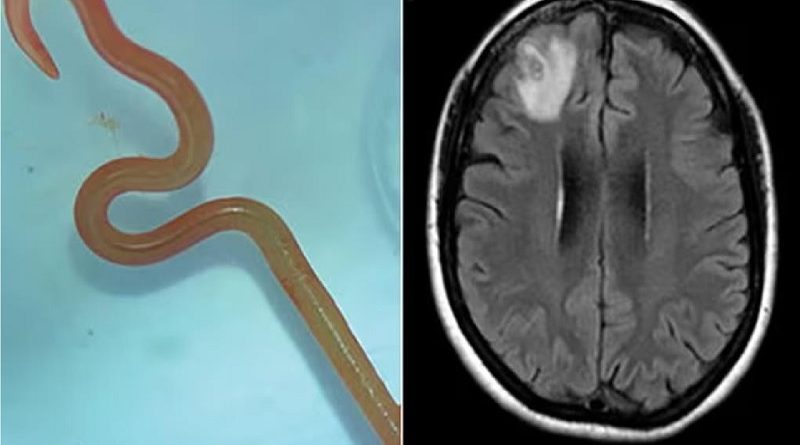

Verme com 8 cm é encontrado em cérebro humano: “Está vivo e se mexe”

O caso inédito ocorreu no hospital de Canberra, na Austrália (Foto:© Reprodução Canberra Health). Uma mulher de 64 anos, natural